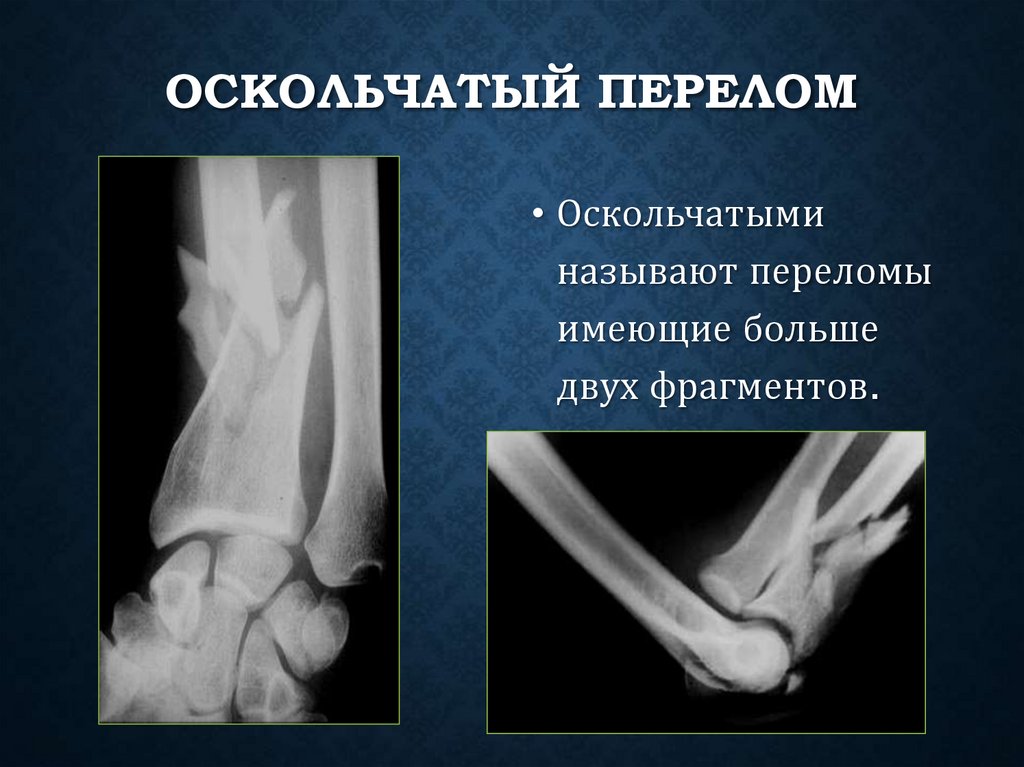

ОСКОЛЬЧАТЫЙ ПЕРЕЛОМ

• Оскольчатыми

называют переломы

имеющие больше

двух фрагментов.